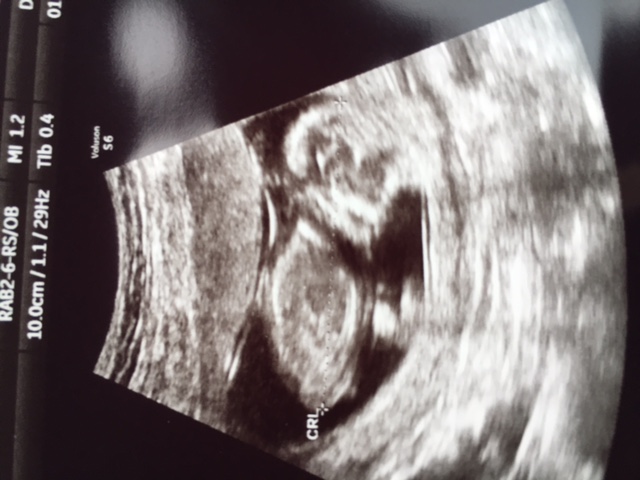

I had another scan today (yes I'm crazy) at 13 weeks and she really saw a girl!!

She didn't doubt about it!

I'll try to put some pictures in here.

I don't see anything in it ;-). when she showed me it at the screen I could see it was a girl, but now I have to look for myself I don't see it ;-)

It are printscreens, because she gave an usb stick with the "movie" from 15 minutes that I could take a look at our little baby.

Looks like a girly nub on the first two pics (left hand side).

Are the first two pics potty shots?? Looks like girl potty shots to me.

The important thing is that the blood test already SAID girl and now we have confirmation by a tech who seemed to be confident and knowledgeable.